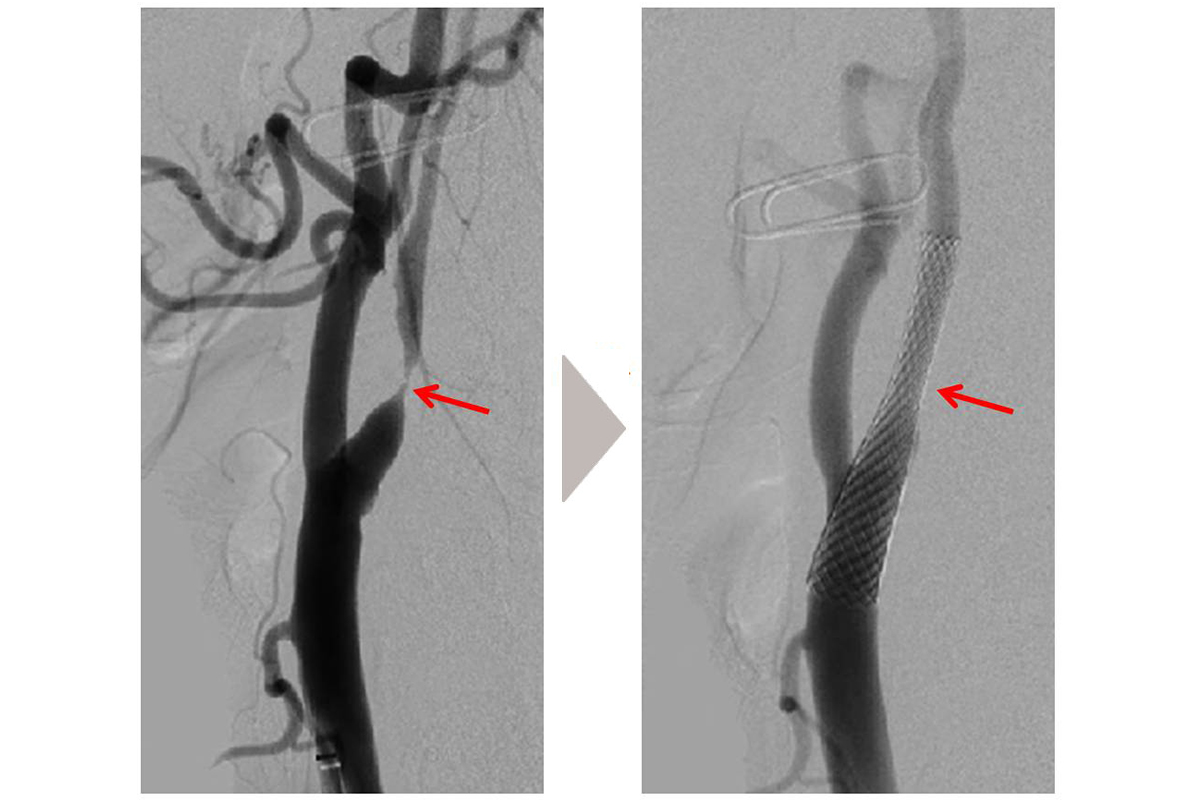

脳神経外科 概要 スタッフ紹介 疾病・治療 疾病・治療 一覧を見る 脳卒中の急性期治療〜脳梗塞に対するカテーテル治療〜 脳外科医がお話しする特発性正常圧水頭症 診療科・部門 診療科 内科 肝臓内科 糖尿病内科 脳神経外科 整形外科 リハビリテーション科 眼科(府中アイセンター) 泌尿器科 泌尿器科(透析センター) 看護部 看護部 薬剤科 薬剤部 診療技術部 放射線室 臨床検査室 リハビリテーション室 栄養管理室 臨床工学室 感染制御室・医療安全管理室 感染制御室 医療安全管理室 地域連携・在宅療養支援部 地域医療連携室 医療福祉相談室 管理部 医療情報課 総務課 府中病院附属きらら保育所